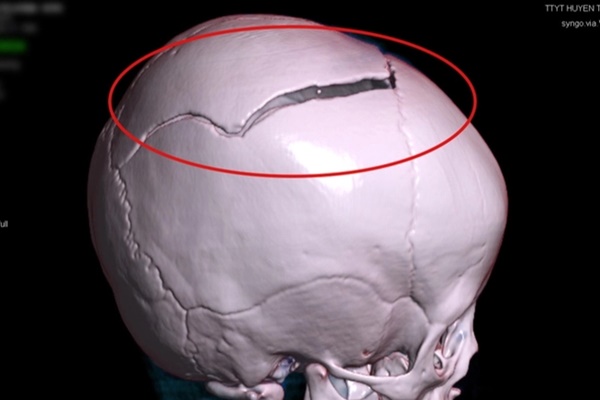

Hình ảnh vùng sọ não bị lún của trẻ trước và sau khi phẫu thuật (vùng khoanh tròn màu đỏ). (Ảnh: Bệnh viện Việt Nam - Thụy Điển Uông Bí)

Các bác sĩ khi thăm khám trên phim chụp CT.Scanner sọ não phát hiện, trẻ bị vỡ lún xương sọ trán phải, đụng dập tụ máu nhu mô não trán phải. Bệnh nhi được phẫu thuật nâng lún xương sọ, cầm máu và xử trí vết thương.